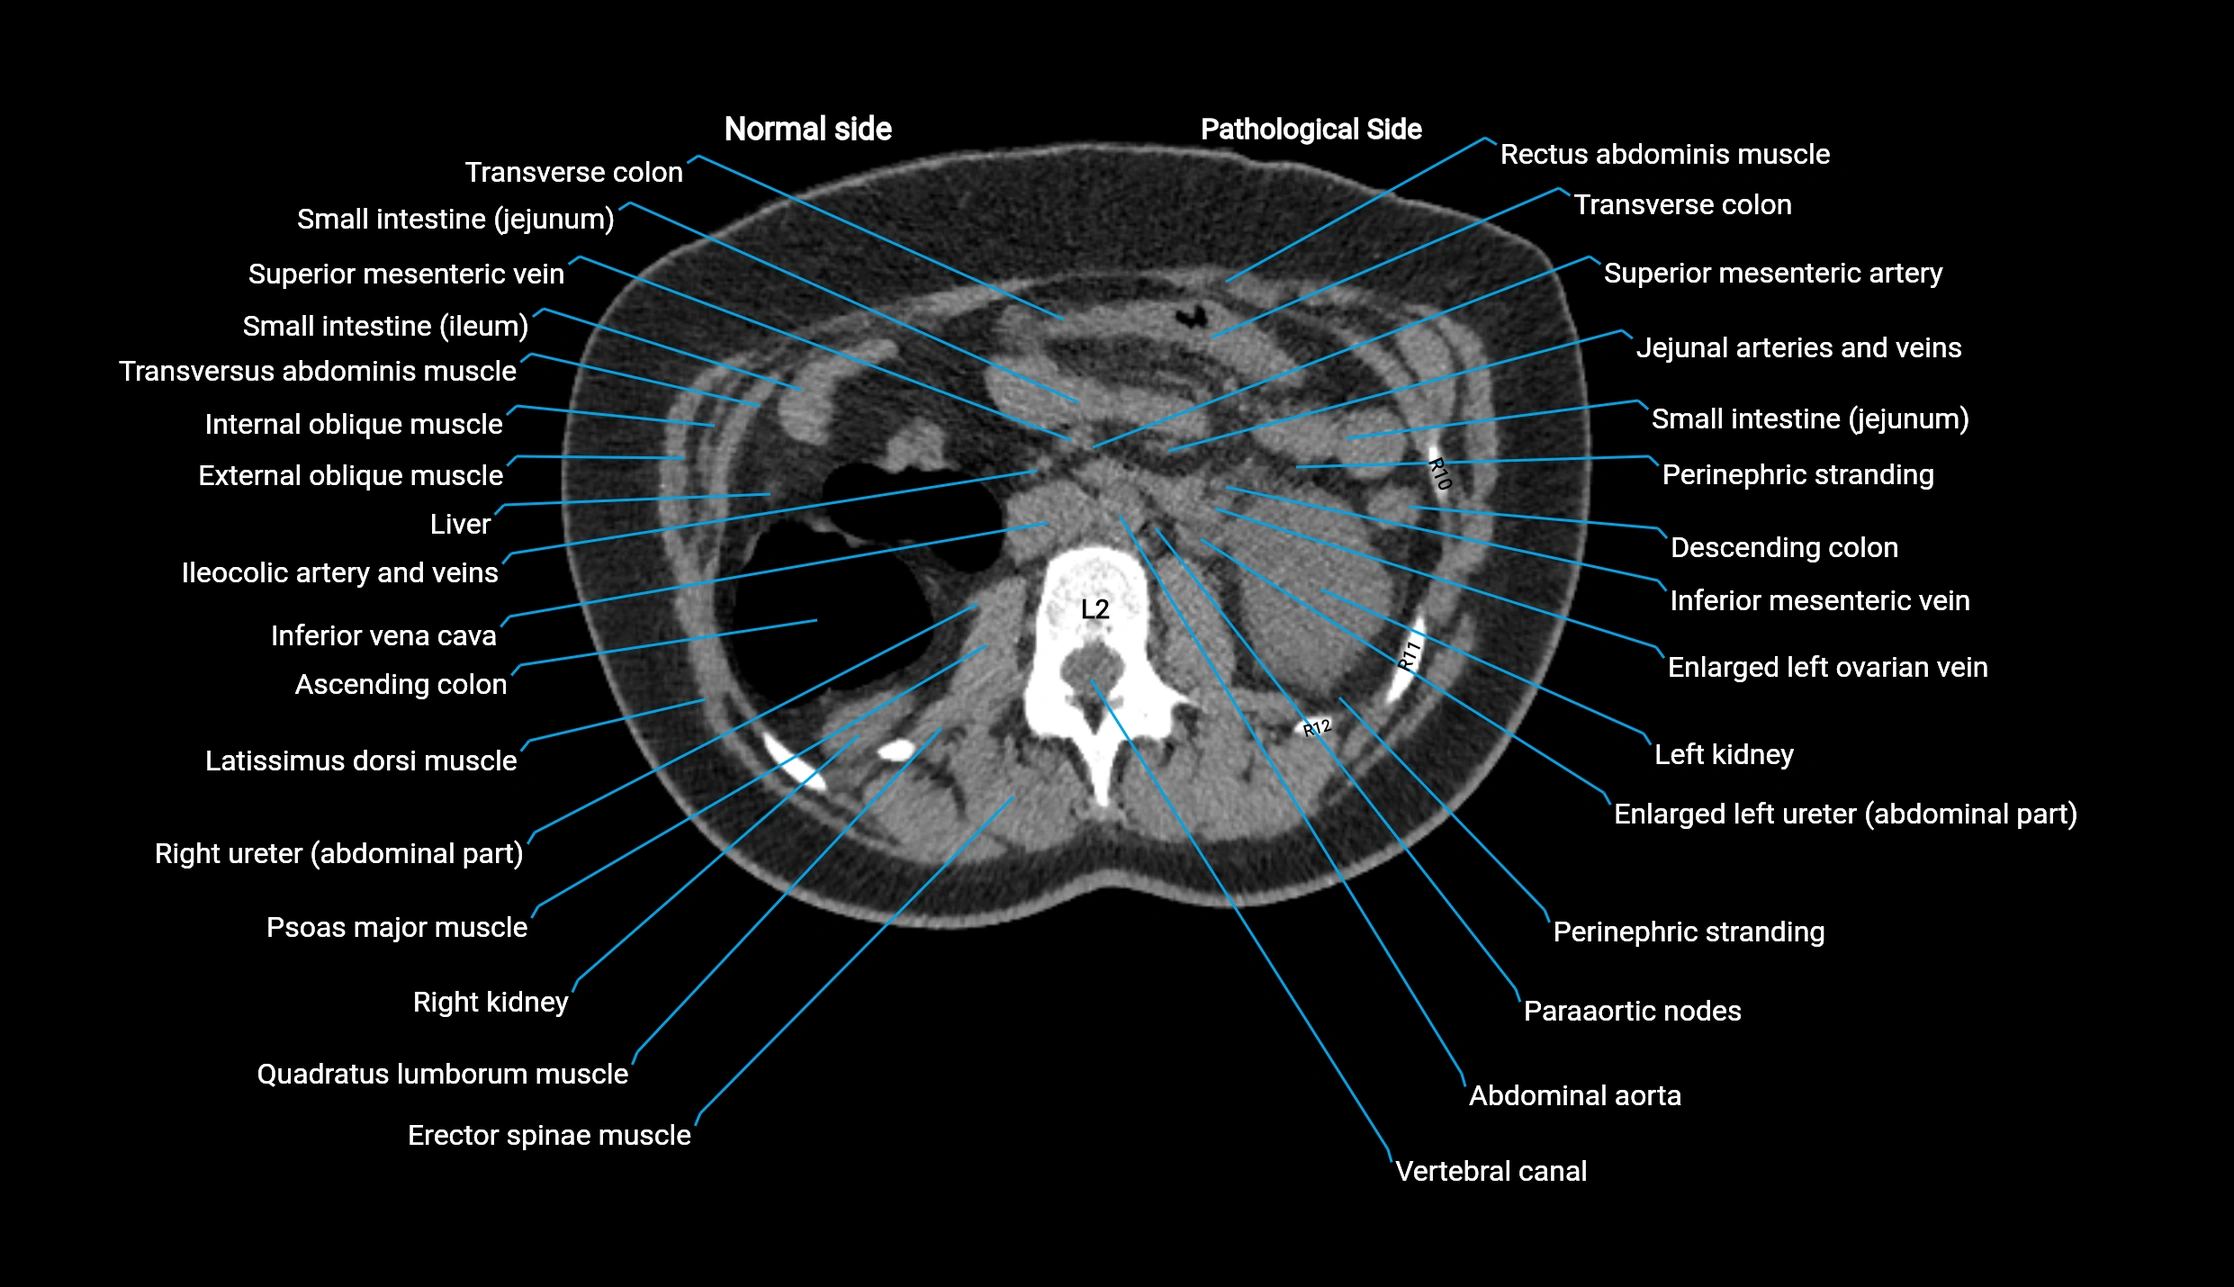

CT image

image